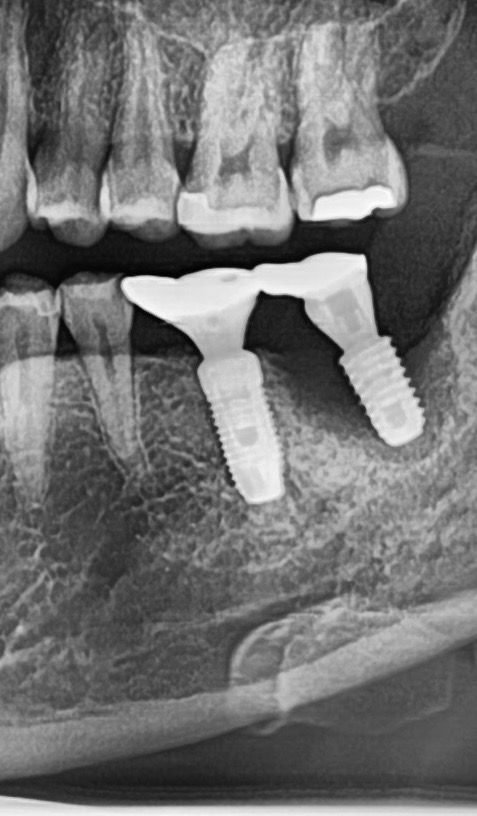

임플란트 주위염으로 녹은 잇몸뼈.. 꼭 임플란트를 제거해야하나요

최근 급격하게 안좋아진 잇몸으로 치과에 방문했다가 지금 임플란트밑으로 고름이 찼고 잇몸뼈가 다 녹아서 옆에 치아에 번지기 전에 하루빨리 임플란트를 제거하고 뼈가 차오르길 기다렸다가 뼈이식한후 임플란트를 다시 해야한다는 소견을 받았습니다 (캐나다 거주중, 현지 치과 방문)

• 1번 째 사진

사진에 보이는 임플란트는 주변잇몸뼈가 다 녹아 있는상태 입니다. 제거를 하시는게 좋을것같습니다.

허나 엑스레이 사진을 보면 염증으로 이미 뼈가 대부분 녹았습니다. 저건 임플란트 제거 말고 답 없습니다.